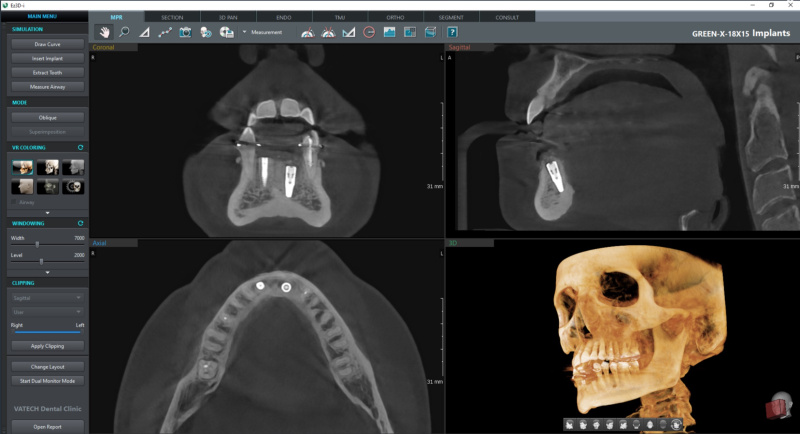

Nowoczesny tomograf Vatech Green X (model 2025) – bezpieczny także dla dzieci

Dokładne obrazy 2D i 3D – niezbędne w chirurgii, ortodoncji, endodoncji i laryngologii

Szybkie skanowanie CBCT – 2,9 sekundy

Nowoczesna tomografia 3D twarzoczaszki – zębów, kości, zatok i stawów. Badanie jest szybkie, bezbolesne, a skan trwa zaledwie 2,9 sekundy.